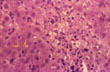

Lymphocytic spillover

Fig 60 - LYMPHOCYTIC SPILLOVER: In case of acute hepatitis A. There is no peripolesis nor rosetting fibrosis.